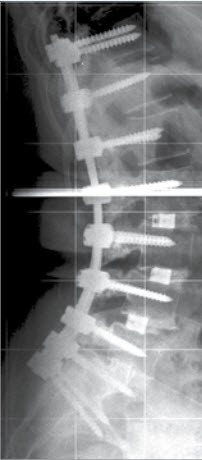

Die Versteifung eines oder mehrerer Segmente der Wirbelsäule basiert auf der Annahme, dass durch Ruhigstellung eine Schmerzverminderung stattfindet. Zudem kann eine Fehlstellung durch eine Versteifung korrigiert und gehalten werden. Versteifungen werden in der Regel mit Metallimplantaten aus Titan (Schrauben, Stangen) vorgenommen (Abbildungen). Diese werden während der Operation an den Wirbeln fixiert und dienen der Sofortstabilität. Die erforderliche Langzeitstabilität wird jedoch durch zusätzliches Anlagern von Knochenmaterial – gewöhnlich aus dem Beckenknochen des Patienten – erreicht (Abb. 1 bis 4). Unter dem Bewegungsschutz der Metallimplantate kann dieser Knochen einwachsen und sich verfestigen.